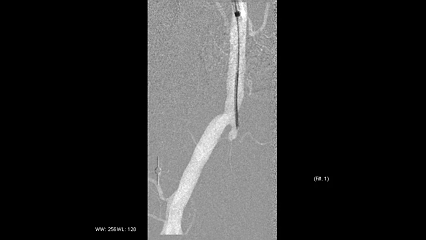

穿刺左侧股总动脉翻山,置入6F翻山鞘行步进造影,显示右侧股浅动脉起始至中远段全程闭塞,腘动脉及膝下流出道尚可。

图:穿刺后造影